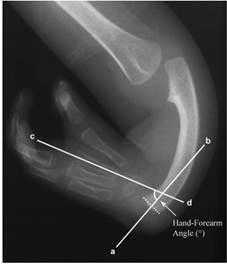

При поступлении в отделение всем пациентам выполняли рентгенограмму предплечья с захватом кисти и локтевого сустава в двух стандартных проекциях. На рентгенограмме предплечья, выполненной в передне-задней проекции, рассчитывали угол лучевой девиации кисти (HFA°), как угол между продольной осью локтевой кости и продольной осью третьей пястной кости (рис. 1) [6].

Рис. 1. Измерение HFA на рентгенограмме предплечья, выполненной в стандартной передне-задней проекции [6]